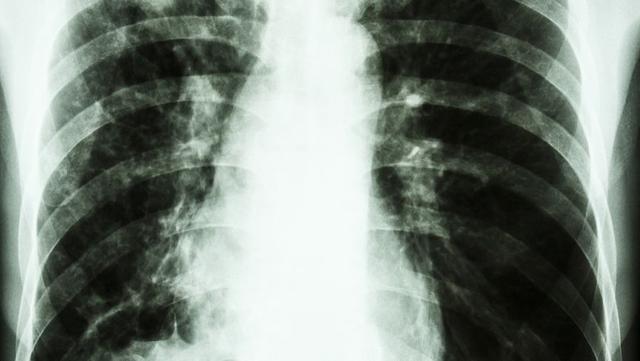

在日常体检中,越来越多的人被发现存在肺结节,这一现象让不少人感到紧张和不安。事实上,大多数肺结节属于良性病变,但仍有一部分可能与早期肺癌相关。因此,了解肺结节可能伴随的异常信号,对于早期识别潜在风险具有重要意义。

值得强调的是,低剂量螺旋CT筛查在肺结节的早期发现中发挥着关键作用。研究表明,与传统胸部X线检查相比,低剂量CT能够将肺癌的早期检出率提高20%以上,并显著降低死亡率。尤其是对于高风险人群,如长期吸烟者或有家族史的人群,定期进行筛查具有重要意义。